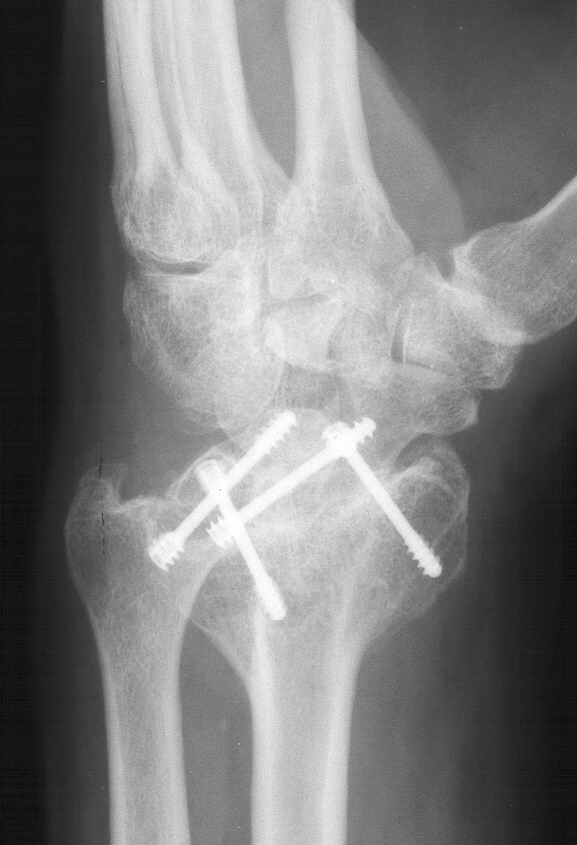

Clinical Example: Radioscapholunate Fusion and Triquetrum excision for Radiocarpal Arthritis

Radioscapholunate fusion is a treatment option for radiocarpal arthritis following distal radius fracture or associated with rheumatoid arthritis. Range of motion is usually less than half of normal following this procedure. Technical modifications to improve range of motion include distal scaphoid excision, or as in this case, triquetrum excision and excision of distal ulnar articular surface to manage ulnolunate abutment. There are a variety of fixation techniques. In this case, crossed Herbert screws were used: dorsal carpal bone to palmar radius and dorsal radius to palmar carpal bone.

Preoperative Xrays: